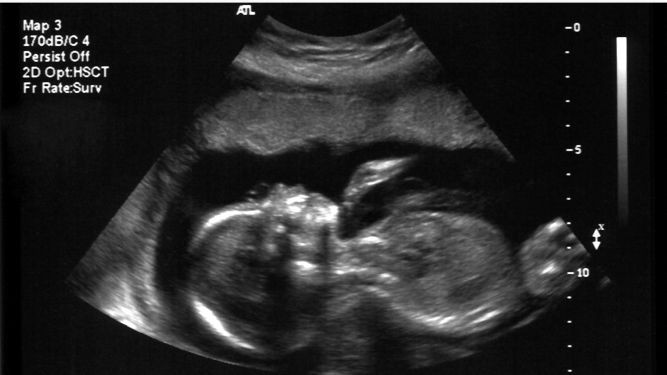

Магичниот момент кога бебето „се јавува“ од стомакот

Првото движење на бебето во стомакот на мајктаа е еден од најемотивните моменти за идните родители.

Фото:Canva/Првото движење не е само физички момент. Тоа е твоето „те слушам, бебе“. Твоето „не сум сама“. Тоа е почеток на приказна.

Иако бебето почнува да се движи многу рано, уште во првите недели од развојот, жената обично не може веднаш да ги почувствува тие мали „акробации“ во стомакот. Тој прв сигнал често се опишува како „пеперутки“, меурчиња или нежно галење одвнатре, момент што многумина го паметат цел живот.